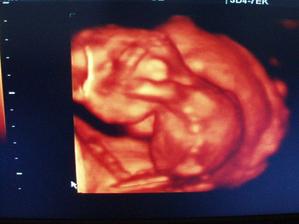

Tak i konečně já přidávám pár svých fotek a postupně budu přidávat další🙂)na prvním utz (fotce) ještě není moc vidět, ale máme srdíčko, jupíííí, zato na druhé už se nám budulínek pořádně ukázal, hip hip hurá🙂))